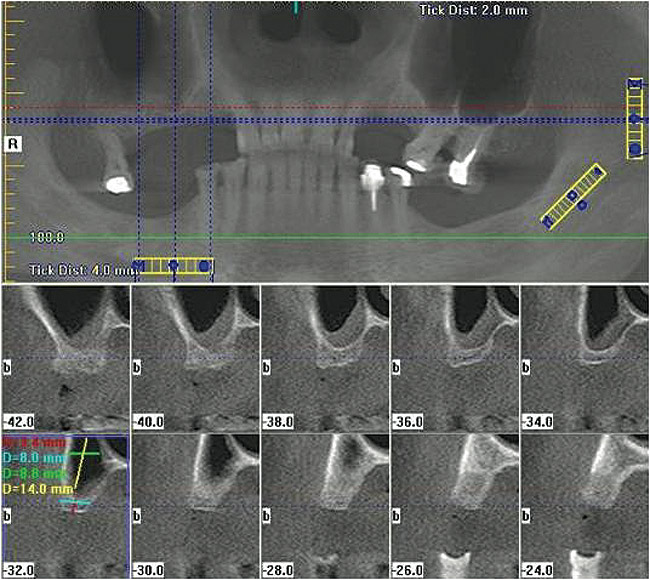

Figure  5  A cone-beam scan was performed prior to the lateral window sinus lift.

Figure 5

Figure  6   A cone-beam scan was performed after the lateral window sinus lift.

Figure 6